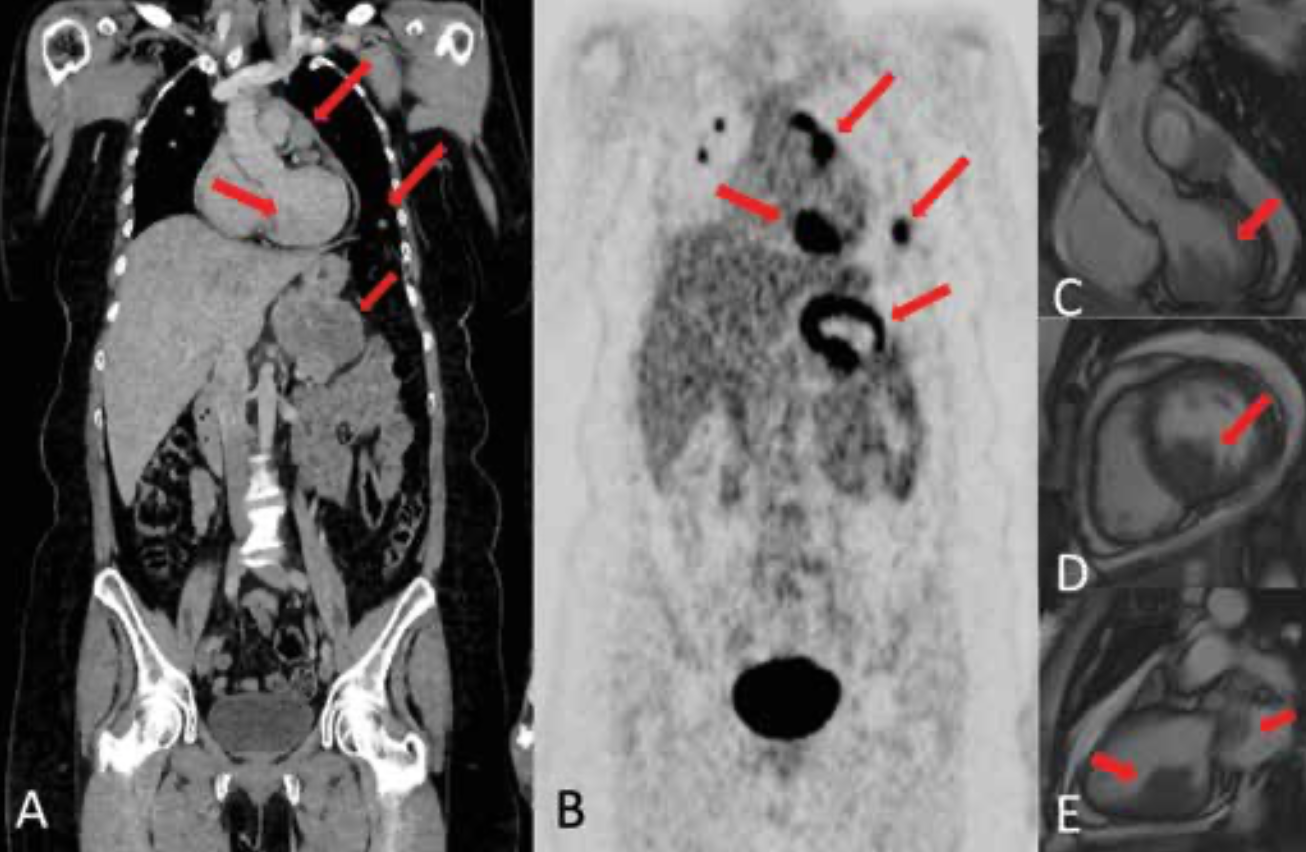

This clinical quandary discusses oligoprogressive disease in metastatic melanoma and how treatment with immunotherapy and targeted therapy affect the disease.